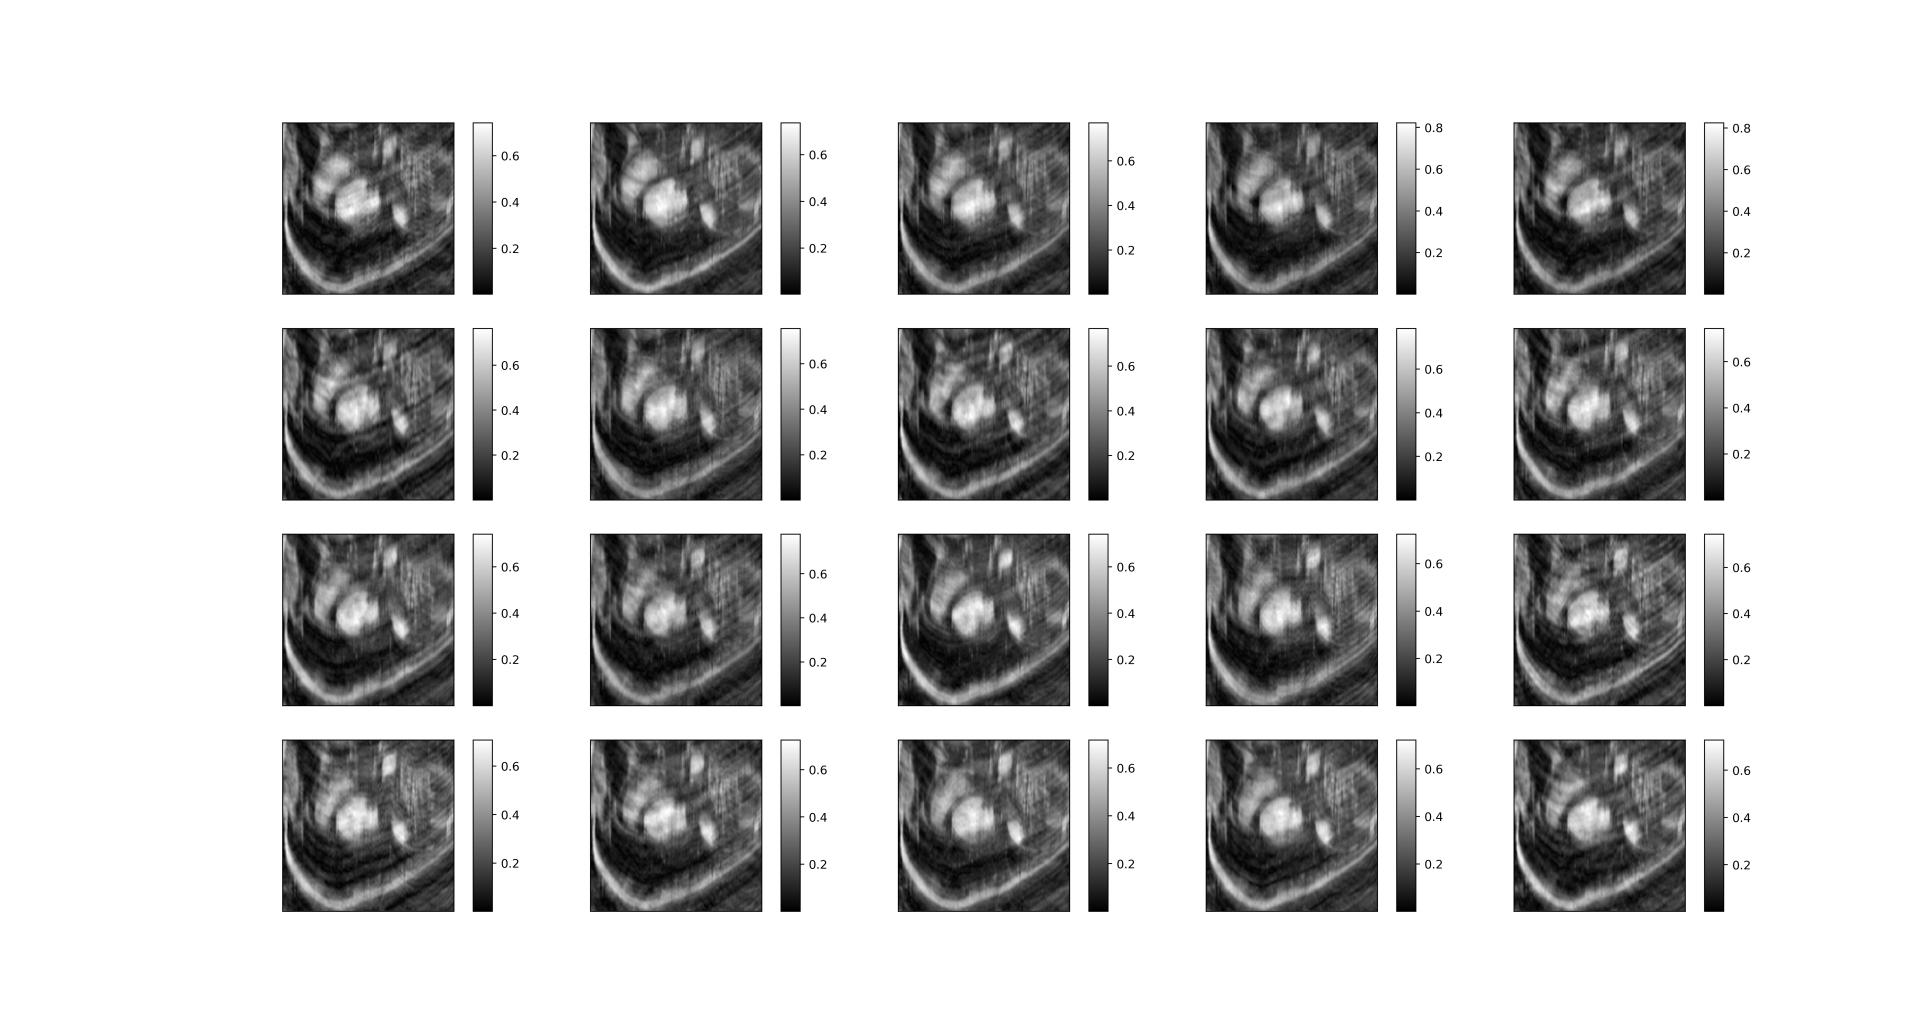

imsshow(mask[0, :, :, :], num_col=5, cmap='gray')The output is in Graph 1.1. We can clearly see that the undersampling mask for dynamic frames differs.

| Graph 1.1 undersampling mask for different dynamic frames |

|---|